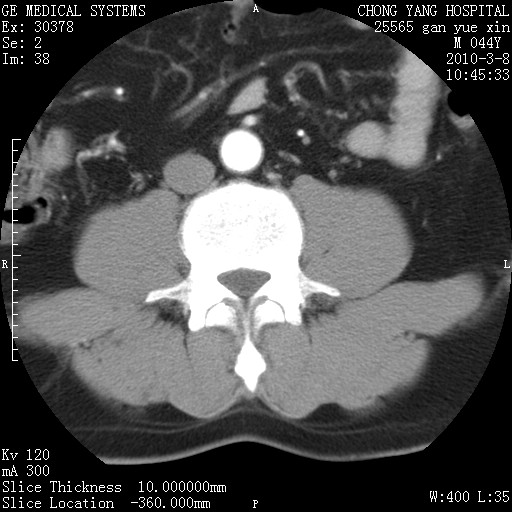

标题: CT24940:主动脉增强,典型病例。 [打印本页]

标题: CT24940:主动脉增强,典型病例。

夹层动脉瘤。

动脉夹层

夹层动脉瘤,典型

主动脉夹层。

动脉夹层的分型:

⒈debakey分型:根据主动脉夹层累及部位,分为三型:ⅰ型:原发破口位于升主动脉或主动脉弓部,夹层累及升主动脉、主动脉弓部、胸主动脉、腹主动脉大部或全部,少数可累及髂动脉。ⅱ型:原发破口位于升主动脉,夹层累及升主动脉,少数可累及部分主动脉弓。ⅲ型:原发破口位于左锁骨下动脉开口远端,根据夹层累及范围又分为ⅲa,ⅲb。ⅲa型:夹层累及胸主动脉。ⅲb型:夹层累及升主动脉、腹主动脉大部或全部。少数可累及髂动脉。

⒉stanford分型:a型:夹层累及升主动脉,无论远端范围如何。b型:夹层累及左锁骨下动脉开口以远的降主动脉。

夹层动脉瘤,少量胸水

夹层动脉瘤;左侧少量胸腔积液。

典型主动脉夹层。